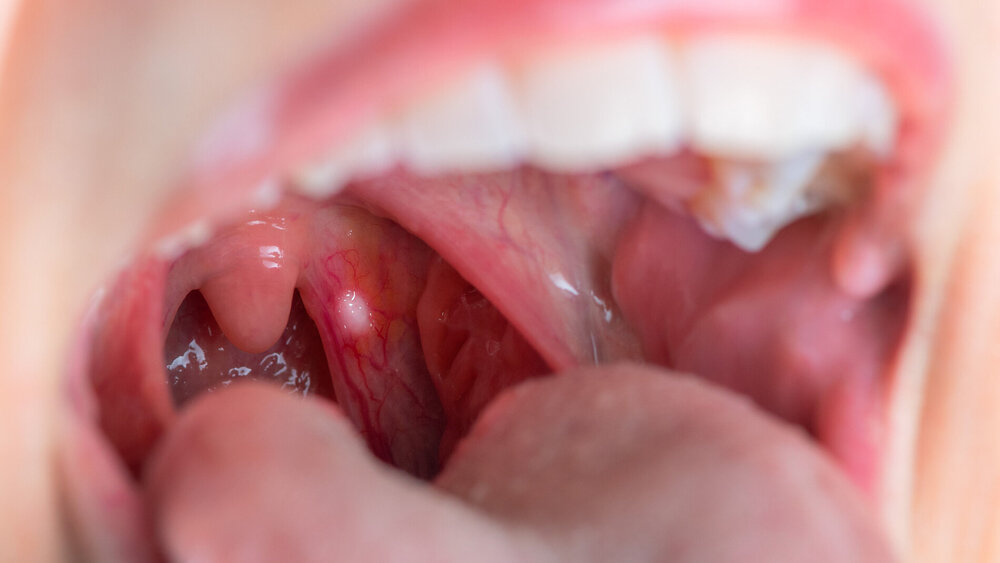

Wie das Statistische Bundesamt meldet, sind 2022 sind rund 231.500 Menschen an Krebs verstorben. Damit ist die Erkrankung die zweithäufigste Todesursache hierzulande nach Herz-Kreislauf-Erkrankungen und bedingt insgesamt 22 Prozent der aller Todesfälle. In der Altersgruppe der 40- bis 79-Jährigen war diese mit 35 Prozent die häufigste Todesursache. Mehr als die Hälfte aller Krebspatientinnen und -patienten sind zwischen 60 bis 79 Jahre alt. An Krebs in Mundhöhle und Rachen erkrankten im Jahr 2022 rund 4.900 Frauen und 9.700 Männer neu.